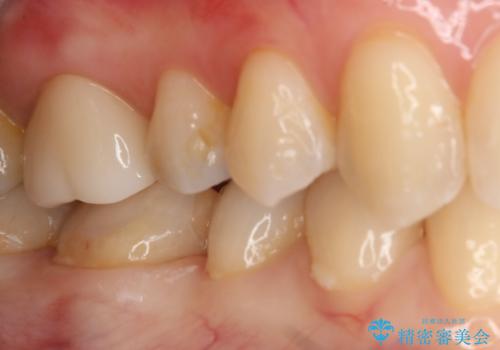

銀の詰め物が取れた セラミックインレー治療

- 右下6番のメタルインレー脱離のため来院。

セラミックの治療を希望されたため切削量を考慮し、セラミックインレーでの治療を選択しました。

う蝕が深くまで進行していたので、CRで裏層した上で形成・印象をしています。